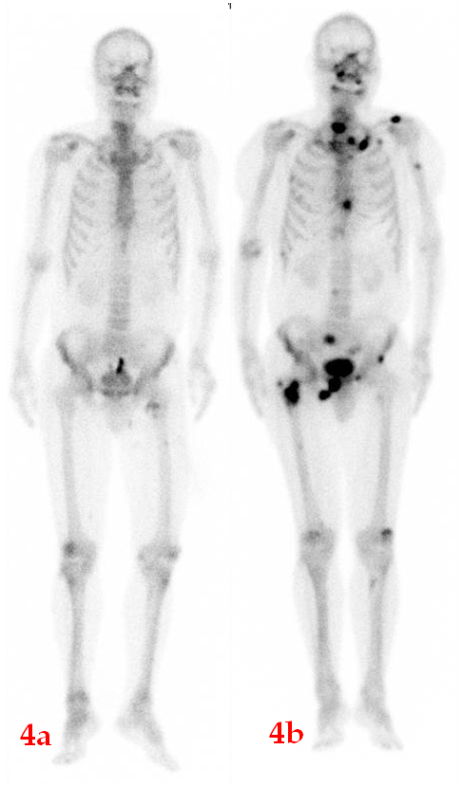

肺腺癌患者,2018年12月ECT檢查(4a圖)未見明顯異常;期間未復查;2023年5月骨痛來診,ECT檢查(4b圖)顯示全身多發骨轉移。